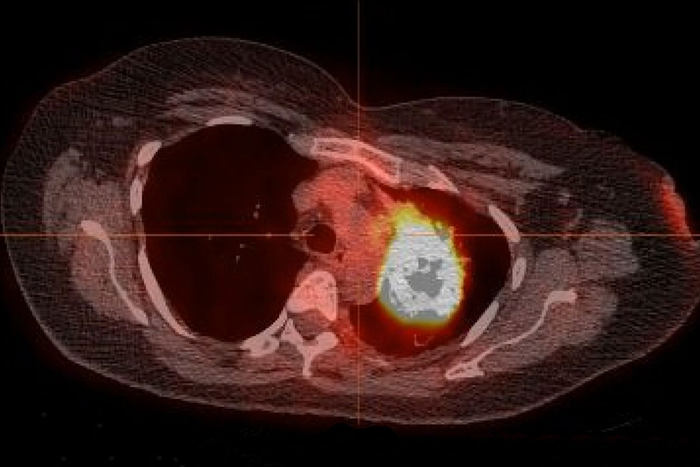

Peer-Reviewed PublicationIMAGE: PICTURED ABOVE IS A RADIOGRAPHIC IMAGE OF A LUNG TUMOR IN A PATIENT WHO NEVER SMOKED BUT STILL DEVELOPED LUNG CANCER. A NEW STUDY FROM WASHINGTON UNIVERSITY SCHOOL OF MEDICINE IN ST. LOUIS ESTIMATES THAT 78% TO 92% OF LUNG CANCERS IN PATIENTS WHO HAVE NEVER SMOKED CAN BE TREATED WITH PRECISION DRUGS ALREADY APPROVED BY THE FOOD AND DRUG ADMINISTRATION TO TARGET SPECIFIC MUTATIONS IN A PATIENT’S TUMOR. view more

CREDIT: WASHINGTON UNIVERSITY SCHOOL OF MEDICINE